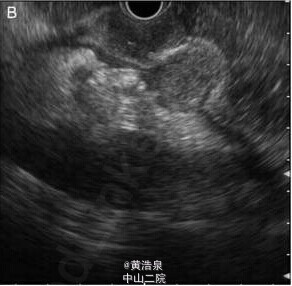

患者,男性,47 岁,消化不良、上腹部不适 2 个月,伴有体重减轻约 4kg,无消化道出血,无发热、咳嗽。既往无疾病、手术史。体格检查无明显异常。实验室检查示:血红蛋白 114g/L,血沉增快 54mm/h,无 HIV、乙肝和丙肝病毒感染。心电图、胸片无异常。 胃镜示:胃体处可见多个粘膜下肿物 (SEL)(图 1A),贲门、胃窦粘膜正常。血中嗜铬粒蛋白 A 和尿液中 5 羟基吲哚乙酸水平正常。行超声内镜检查(图 1B) 并于引导下行肿物穿刺,穿刺吸取物送检细胞学样本如图 2。 超声内镜显示胃壁内固有肌层处,可见多个大小约 1.5-2cm 界限清楚的低回声区,中心呈现高回声,伴有固有肌层的破坏 (图 1B),无胃周脏器及纵膈淋巴结累及。 穿刺吸取物细胞学检查显示为肉芽肿病变 (图 2),ZiehlNeelsen 染色示与结核分枝杆菌形态学一致 (图 3),培养后证实与染色结果一致。 超声内镜引导下肿物穿刺并送检细胞学检查及培养最终确诊为胃结核。 (来源:丁香园)